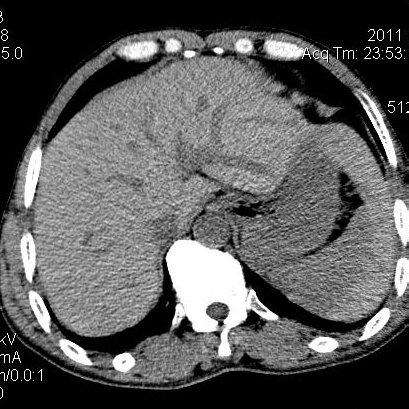

肝左叶发育异常

男性,55岁,骑摩托车摔倒后入院,自述右上腹疼痛

[backcolor=#FF0000]第一次诊断的时候也是这么肯定,可是床旁超声检查并没有发现明显异常,而且患者的一般症状都良好。还好临床只是保守治疗,没有立即手术,第二次复查的时候没有一点变化,又做了MRI检查,没有血肿,

这是一例肝左叶发育异常的,很个性吧~[/backcolor]